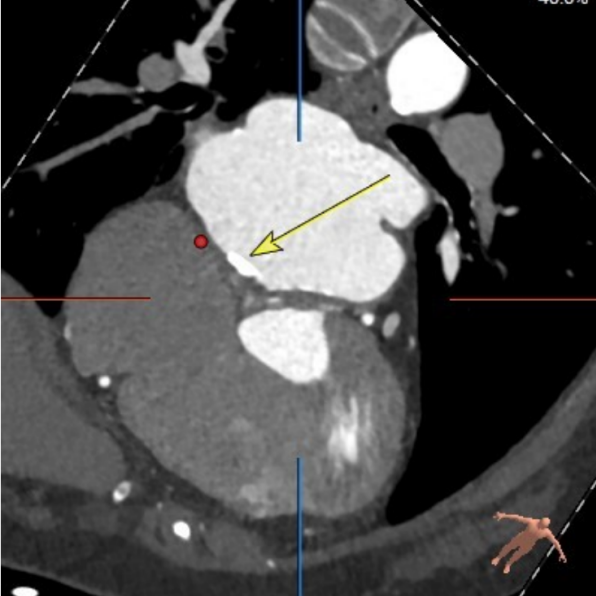

二尖瓣生物瓣架内径23mm,外径25mm,根据瓣架形态,符合25#Mosaic瓣膜

模拟23#Renatus植入

模拟25#Renatus植入